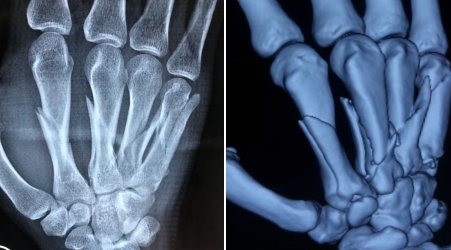

7月20日晚,蒋先生(化名)急匆匆赶到betway在线登陆,挂了手外科的号。手外二病区的熊祖国医生正值班,他接诊并查看了蒋先生病情,为其做了检查,X光片显示蒋先生右手第2-5掌骨粉碎骨折,骨折端移位明显;右示指中节骨折。

术前